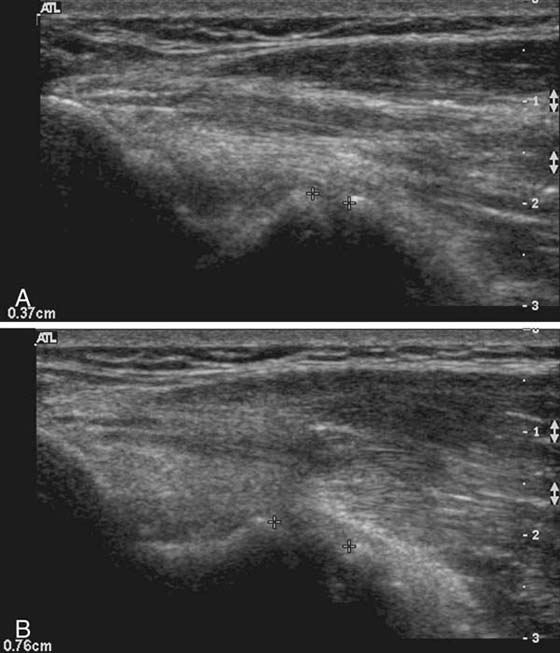

Lateral epicondylitis, or “tennis elbow,” is a chronic tendinopathy of the common extensor origin and is a frequent cause of lateral elbow pain. On MRI, abnormal high signal is seen at the common extensor origin on fluid-sensitive sequences, sometimes with associated partial tears, which are fluid-bright.29 In more severe cases, associated subtendinous bone marrow edema may be present at the lateral epicondyle, but this is not required for radiologic diagnosis. US is a valuable modality for examining the lateral epicondyle.30,31 Sonographic features include common extensor origin thickening, heterogeneous echogenicity, calcific deposits, partial tears, and hypervascularity on Doppler imaging (Fig. 14-12). US may also be used to guide steroid or anesthetic injections and tendon fenestration.32 Medial epicondylitis has similar MRI and US findings at the common flexor origin. Both of these entities may be associated with injury to the adjacent medial and lateral stabilizing structures.33 Evaluation of the other tendons, including the biceps, triceps, and brachialis, is optimized with MRI. US is also useful for directed examination of tendon pathology at the elbow.

images

Figure 14-12 Lateral epicondylitis or common extensor tendinosis with partial tear. Ultrasound image demonstrates thickening of the common extensor origin consistent with tendinosis/epicondylitis with an associated hypoechoic (black) defect within the extensor tendon origin consistent with an interstitial partial tear (arrow). Power Doppler imaging demonstrates hypervascularity (orange areas), often seen with lateral epicondylitis/common extensor tendinosis.